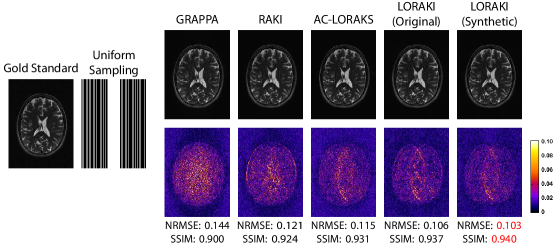

Figureย 2, Tableย 1, and supporting Fig.ย S1 show results from reconstructing uniformly-undersampled T2-weighted data. In this specific case, we simulated an acquisition that measured every fourth line of k-space, while also fully-acquiring the central 32 phase encoding lines to be used as ACS data. Taken together, this results in an effective acceleration factor of 2.6ร—2.6\times. As can be observed from Fig.ย 2 and Tableย 1, the proposed LORAKI approach had the best performance in all cases, with uniformly lower NRMSE values and uniformly higher SSIM values compared to GRAPPA, RAKI, or AC-LORAKS. We observed similar NRMSE and SSIM values for LORAKI when using the original ACS data or when using synthetic ACS data generated from an initial AC-LORAKS reconstruction of the data. In this specific case, the amount of acquired ACS data is already relatively high, which may explain the relative lack of impact from using synthetic ACS data. A corresponding ESP plot shown in supporting Fig.ย S1 shows that LORAKI approaches have consistently similar or better error characteristics than other methods across all spatial frequencies, with the most significant advantage at high-spatial frequencies.

Figureย 3, Tableย 2, and supporting Fig.ย S1 show results from reconstructing randomly-undersampled T1-weighted data. In this specific case, we simulated an acquisition with an effective acceleration factor of 5.2ร—5.2\times (including samples from a fully-sampled 64ร—64646464\times 64 ACS region at the center of k-space). Similar to the previous case, LORAKI had uniformly smaller NRMSE and larger SSIM values compared to AC-LORAKS, with the most significant error improvements at high spatial frequencies. GRAPPA and RAKI reconstruction were not performed in this case, due to the large number of local sampling configurations resulting from random sampling. As before, there was not a big difference between using the original ACS data versus using synthetic ACS data, which might be explained by the relatively large size of the acquired ACS data.

Figure 2: Representative reconstruction results for uniformly-undersampled T2-weighted data. The top row shows reconstructed images for one slice in a linear grayscale, where the gold standard image has been normalized to range from 0 (black) to 1 (white). The bottom row shows error images with the indicated colorscale. NRMSE and SSIM values are also shown below each image, with the best values highlighted in red.

Figure 3: Representative reconstruction results for randomly-undersampled T1-weighted data. The top row shows reconstructed images for one slice in a linear grayscale, where the gold standard image has been normalized to range from 0 (black) to 1 (white). The bottom row shows error images with the indicated colorscale. NRMSE and SSIM values are also shown below each image, with the best values highlighted in red.